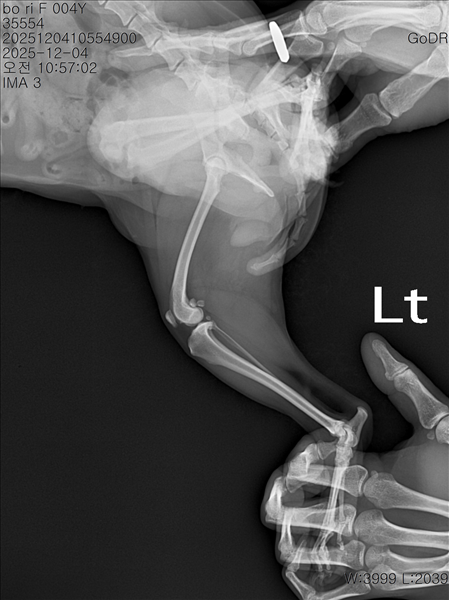

강아지 슬개골탈구 진단 받았습니다 몇군데 병원을 다녀봤는데 진단이 달라 궁금해서 질문 해봅니다 일단 저희 강아지는 오른쪽 다리를 갑자기 들고 다니고 절어 병원을 방문하게 되었고요 왼쪽은 증상이 없지만 오른쪽만 있는 상태였습니다 첫번째랑 두번째 병원에서는 슬개골 탈구 진행중이고 왼쪽이 3기 오른쪽이 2기 정도라고 했습니다 하지만 왼쪽은 아예 빠져있어 증상도 없고 아파하지도 않는다고 했고 오른쪽은 빠졌다 안빠졌다 해서 증상이 있다고 했고 십자인대가 파열된 걸론 보이지 않는다고 했습니다 그래서 양쪽 슬개골탈구 수술만 진행하면 된다고 했고요 근데 세번째 병원에서는 둘다 왼쪽이 좀 더 심한 슬개골 탈구 3기 정도라고 했고 오른쪽만 십자인대 부분파열이 보인다고 했습니다 그래서 십자인대 파열이 아닌 왼쪽은 굳이 수술할 필요가 없고 나중에 십자인대 파열이 오거나 증상이 나타나면 그때 수술하면 된다고 했습니다 그래서 오른쪽 슬개골탈구 수술과 tplo를 하는 방식으로 수술을 한다고 했습니다 여기서 궁금한점은

1. 십자인대 파열이 사진상으론 보이지 않는다고 하는데 사진상으로 알 수 있는 건가요?

4. 사진상으로 십자인대와 슬개골 수술을 같이 해야할까요? 5. tplo 수술방법이 가장 안전하고 좋은 수술방법인가요?